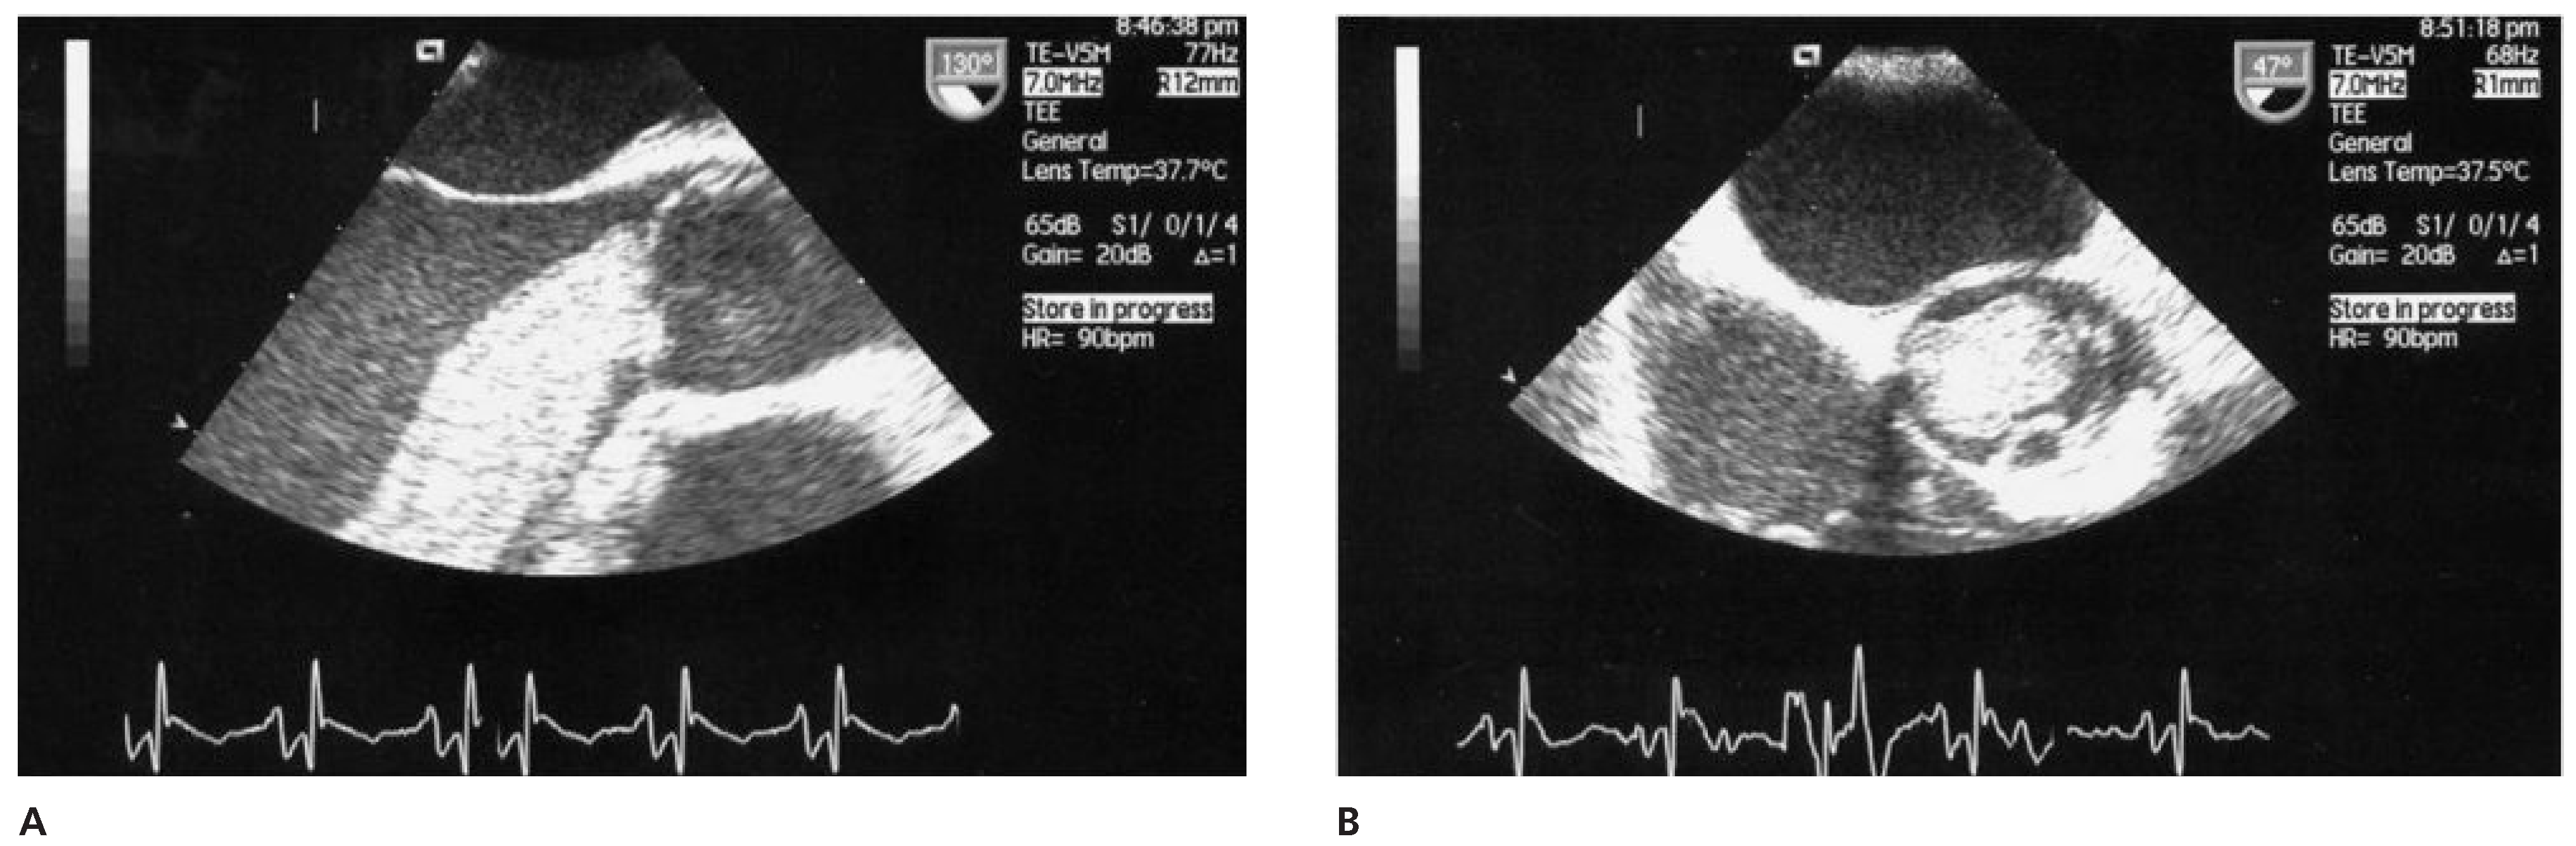

Case report 6: endometrial stromal sarcoma with extension into the right heart